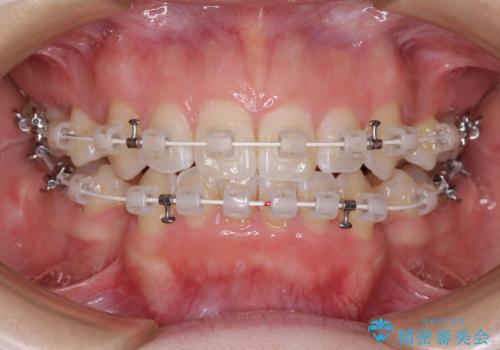

- 矯正装置

- 審美装置

- 1年11ヶ月

- 10-30回